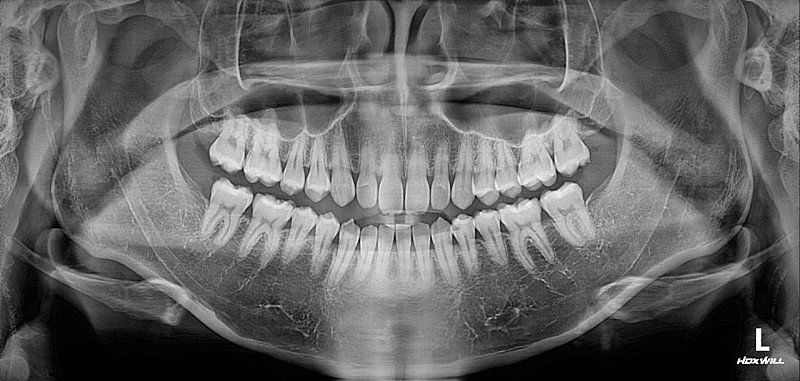

□앞니 치근이 짧다고 들은적이 있는데 교정하다가 더 짧아질까요?

5. 치근 흡수는 교정하게 되면 나타나는 부작용이지만 이를 예측하기는 힘듭니다.

겨정을 하면서 치아의 뿌리가 짧아 지는 경우가 있는데 간단한 교정의 경우에 치근이 흡수될 가능성은 낮습니다.

-부분교정이라면 크게 걱정하실문제는 아니라고 생각합니다.

투명교정정도로는, 치아뿌리가 심하게 흡수되거나 하진 않습니다. 일반적으로 치아를 급격히 이동시키거나 이동량이 많을때 뿌리가 흡수될 수 있습니다.